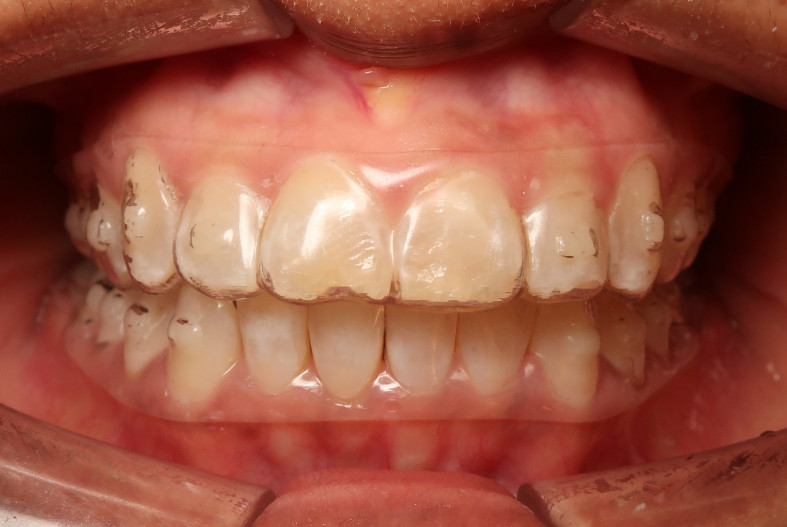

Der intraorale Befund (Abb. 2a–e) sowie die Modellanalyse (Abb. 3a–e) zeigten neben dem Diastema mediale im Oberkiefer vor allen Dingen eine Anteinklination und Supraokklusion beider Fronten. Besonders anterior wiesen beide Zahnbögen eine transversale Enge auf. Dies zeigte sich in einem deutlichen Unterkieferfrontengstand mit Labialkippung des Zahnes 41. Neben Abrasionen und Schlifffacetten, vor allem in der Front, waren auch vereinzelt Gingivarezessionen erkennbar. An Zahn 11 lag eine Schmelzfraktur der Inzisalkante vor. Durch die zwangsgeführte Laterognathie ergab sich eine Mittellinienverschiebung nach rechts von 3 mm. Eine beidseitige Distalokklusion bei vergrößerter sagittaler (6 mm) und vertikaler (5 mm) Stufe war erkennbar. Aufgrund der deutlichen transversalen Zahnbogenenge im Unterkiefer ergab sich links eine Tendenz zum Scherenbiss.

Nach ausführlicher Diagnostik und intensiver Aufklärung über Behandlungsalternativen und -risiken entschied sich die Patientin für eine Behandlung mittels ClearCorrect™ Alignern. Durch die hohe Trimline weisen diese Aligner eine äußerst große Formstabilität auf und eignen sich deshalb besonders gut für transversale Korrekturen und Tiefbissbehandlungen. Neben der ca. zweijährigen kieferorthopädischen Behandlung wurde eine physiotherapeutische Behandlung verschrieben.